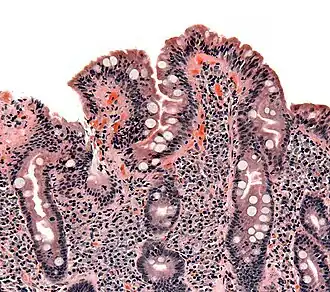

| Biópsia do intestino delgado onde a doença celíaca se manifesta por deformações nas vilosidades, hiperplasia e infiltração de linfócitos nas criptas. | |

As alterações patológicas clássicas da doença celíaca no intestino delgado são categorizadas de acordo com a Classificação de Marsh:[69][70]

- Estádio 0: mucosa normal

- Estádio 1: infiltração linfocitária intraepitelial superior a 20 por cada 100 enterócitos

- Estádio 2: proliferação das criptas intestinais

- Estádio 3: atrofia parcial ou total das vilosidades intestinais e hipertrofia das criptas[71]

- Estádio 4: hipoplasia da constituição do intestino delgado

A classificação de Marsh, introduzida em 1992, foi posteriormente modificada em 1999 para seis estádios, tendo o estádio 3 sido dividido em três sub-estágios.[72] Os estudos posteriores demonstraram que este sistema nem sempre era fidedigno e que as alterações observadas na doença celíaca podiam ser descritas em um de três estágios — A, B1 e B2 — em que A representa a infiltração linfocitária com aparência das vilosidades normal e em que B1 e B2 descrevem a atrofia parcial ou total das vilosidades.[34][73]